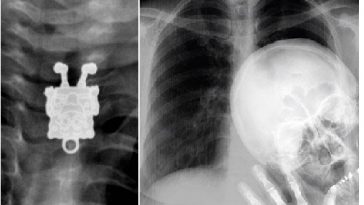

14. 3 parazitická dvojčata v lebce dvouměsíčního dítěte.

3 parazitická dvojčata v lebce dvouměsíčního dítěte

od u/JudgmentPuzzleheaded in medizzy

15. Muži přijeli do nemocnice vlastními silami v taxíku…

Ano, má zlomený vaz.